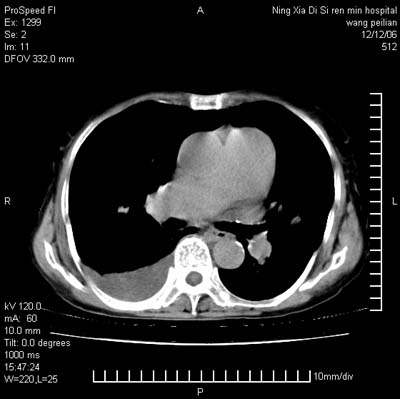

标题: CT5609:胸部:女77 病史不详

两肺可见多个大小不等的结节,左侧有胸水,纵隔淋巴结增大,考虑是细支气管肺泡癌

两肺尖纤维索状影,两下肺结节块状影,且有钙化灶,右胸腔积液。考虑肺结核并胸膜炎。

两肺尖纤维索状影,两下肺结节块状影,且有钙化灶,右胸腔积液。考虑肺结核并胸膜炎肺间质纤维化

考虑:1、慢性支气管炎合并全小叶型肺气肿、间质纤维化;

2、双肺结核;

3、右侧胸膜炎(积液)。

1、双肺继发型肺结核(以纤维、增殖灶为主);

2、右侧胸腔积液;

3、其余符合老年肺改变。

双肺见多个结节状及条索状影,双侧胸腔积液,右侧叶间积液,考虑结核性胸膜炎